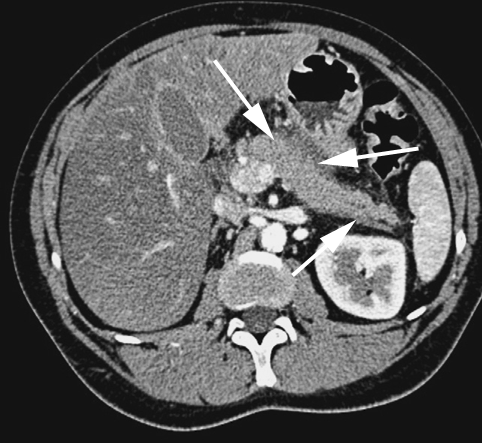

C’est l’examen de référence pour le diagnostic de PA. Elle permet de mettre en évidence un élargissement pancréatique focal ou diffus, une hétérogénéité du parenchyme pancréatique, un flou des contours de la glande pancréatique, une densification de la graisse péri-pancréatique ou un épaississement des fascias périrénaux (Figure n°4 et 6).

Figure n°4 : Pancréatite aigue balthazar B

(flèches pancréas augmenté de volume)

Elle permet de visualiser la nécrose pancréatique sous la forme d’une zone d’hypoperfusion avec une Sensibilité de 80 à 90 % et une Spécificité de 95 à 100 %. Cet élément est considéré comme de grande valeur pronostique mais elle ne doit pas être réalisée trop précocement (avant la quarante-huitième heure) dans les pancréatites aiguës sévères, car elle risque de sous-estimer l’extension de la nécrose.